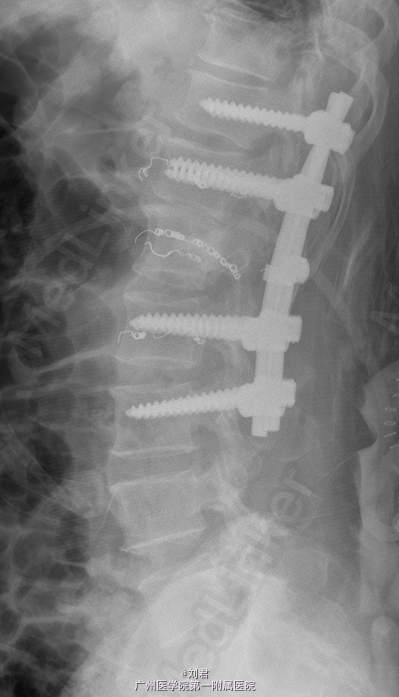

初步诊断:腰椎肿瘤. 手术指征明确,行腹主动脉造影+腰椎动脉超选造影+胸12、腰1、2动脉栓塞术,后行腰椎肿瘤后路肿瘤切除、椎管减压、内固定术。

术后病理:(腰1椎体)血管瘤。术后予抗感染、止痛等治疗。患者术后恢复可,复查腰椎X片示内固定位置可.